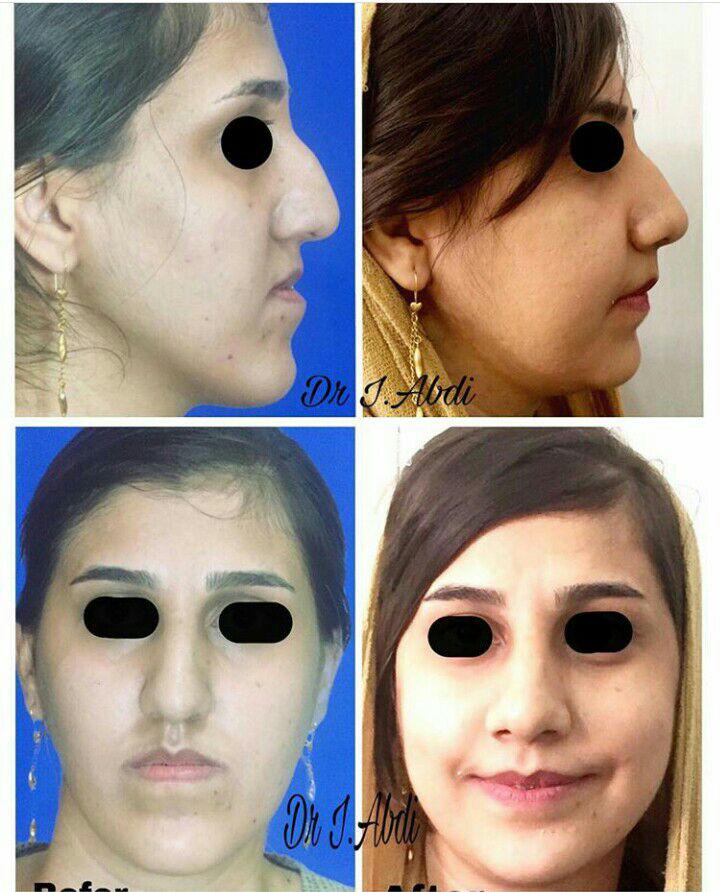

دکتر عیسی عبدی در رشت

دکتر عیسی عبدی در رشت

– متخصص جراحی فک , پلاستیک صورت و بینی

دکتر عیسی عبدی در رشت

جراحی فک , پلاستیک , صورت وبینی